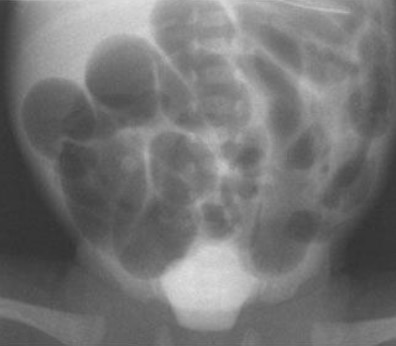

Common abdominal X-ray findings:

Common X-ray Findings: